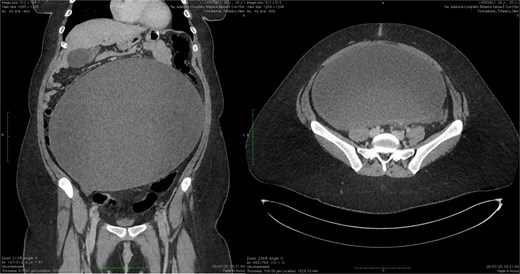

Abdominal ultrasound revealed a large, anechoic mass, apparently multicompartmental, located predominantly on the left side but also extending to the pelvis. A subsequent abdominal CT scan with contrast revealed a large cystic mass measuring approximately 32 × 27 cm, presumably originating from the adnexal region, extending from the mesogastric region to the pelvis. The lesion caused compression on the small intestinal loops, located in the epigastric region but without signs of occlusion, and significant compression of the infrarenal inferior vena cava. No free effusion or signs of metastasis were detected (Fig. 1).

CT scan showing ovarian cyst compressing the small bowel in the epigastrium (longitudinal and transversal section).